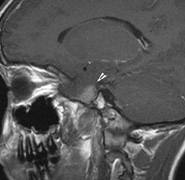

Optic nerve gliomas may involve the optic chiasm and be associated with endocrine disorders or nystagmus.68–70 Surgical excision of chiasmal gliomas (Fig. 6) carries a high risk of visual loss. Invasion of the hypothalamus or the third ventricle carries a poor prognosis, with greater than 50% 15-year mortality rate.71 One review of radiation treatment for chiasmal gliomas collated data from small case series and found no significant long-term improvement in visual function, progression, or mortality with radiation treatment.71 Other reports suggest that radiation doses over 4500cGy improve symptoms and slow progression of chiasmal gliomas over several years.72 Adequate tumor coverage by radiotherapy results in irradiation of normal brain and nearly all children need hormone replacement.73 Chemotherapy is an alternative.74,75

Fig. 6. Surveillance images of a 12-year-old girl with NF1 and an optic nerve glioma which has extended to involve the chiasm. Pre- (a) and postcontrast (b) T1-weighted coronal images reveal a large suprasellar mass with an enhancing component (arrow) seen separately from the normally enhancing pituitary gland. (c) Axial scans through the suprasellar cistern show the tumor is high signal on T2-weighted scans. (d) Enlargement of the chiasm, optic nerve and hypothalamus is visible on the post-contrast T1-weighted sagittal image. Although optic nerve glioma usually has a good prognosis (with visual function often remaining stable in the absence of any intervention66,67), chiasmal involvment is a poor prognostic indicator. A sign of chiasmal involvment may be new onset of endocrine disorders or nystagmus. Surgical excision of chiasmal gliomas carries a high risk of visual loss.68–70